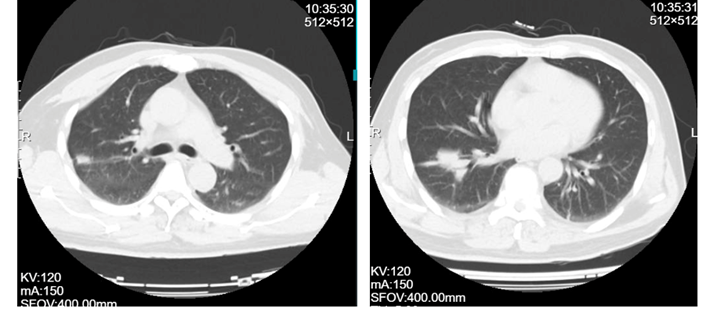

患者男性,62岁,半年前无明显诱因出现胸背部剧烈疼痛,伴下肢无力,严重影响了正常生活。就诊福建当地医院,胸部CT示:右肺下叶前基底段占位,右肺上叶后段类结节样影;T6-9椎体及部分附件多发骨质破坏。骨显像结果示:T6-9椎体显像剂摄取增高,考虑骨转移可能。遂于当地医院行肺部穿刺:(右下叶外基底段活检)结合免疫组化结果倾向腺癌。患者为行进一步治疗,至我院门诊收入病房。

1.T6-9胸椎继发恶性肿瘤(VAS 8分,SINS 11分, ESCC 1c,Tomita 6分,改良Tokuhashi 5分 )

2.肺腺癌(Ⅳ期,T4N1M1)